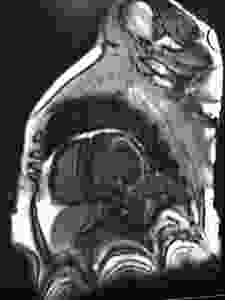

O papel da Ressonância Magnética Cardíaca no Bloqueio Auriculoventricular

https://www.researchgate.net/publication/338663847_P872_A_case_of_transient_atrioventricular_block_the_role_of_cardiac_magnetic_resonance_imaging